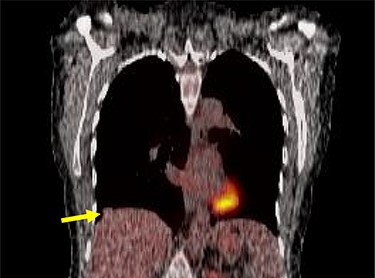

A 54-year-old female without prior thoraco-abdominal trauma presented to the office with two right lower lobe lung nodules. The nodules were initially noted incidentally on a computerized tomography (CT) scan in August 2009 and measured 1.5 cm × 2.8 cm and 0.9 cm × 1.3 cm (Figs 1 and 2). A follow-up CT scan and positron emission tomography (PET) performed in 2010 demonstrated that the nodules were stable in size. The patient was lost to follow-up until March 2019 when she had a CT scan for concern for pneumonia. On these images, the lung nodules had increased in size to 2.8 cm × 4.1 cm and 1.1 cm × 1.4 cm. The patient was otherwise asymptomatic. A PET scan was obtained which showed hypermetabolic nodules with maximum SUV of 3.29 and 1.4, for the larger and smaller nodule, respectively (Figs 3 and 4). Radiographic appearance as well as the growth pattern was consistent with low-grade malignancy suspicious for carcinoid tumor. CT-guided biopsy was not feasible because of location of the tumor.